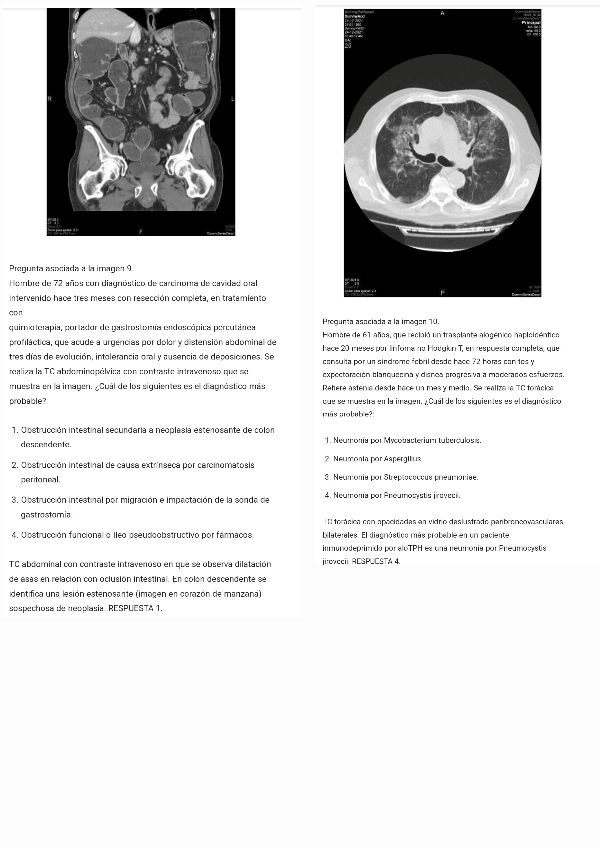

He publicado nuevos apuntes de 4º Radiología y Medicina Física: Caso-clinico-radiologico-de-la-semana.-Dr.-Ramirez.-Del-17-de-abril-al-23-de-abril-a-las-2330-h-Revision-del-intento.pdf

21 páginas